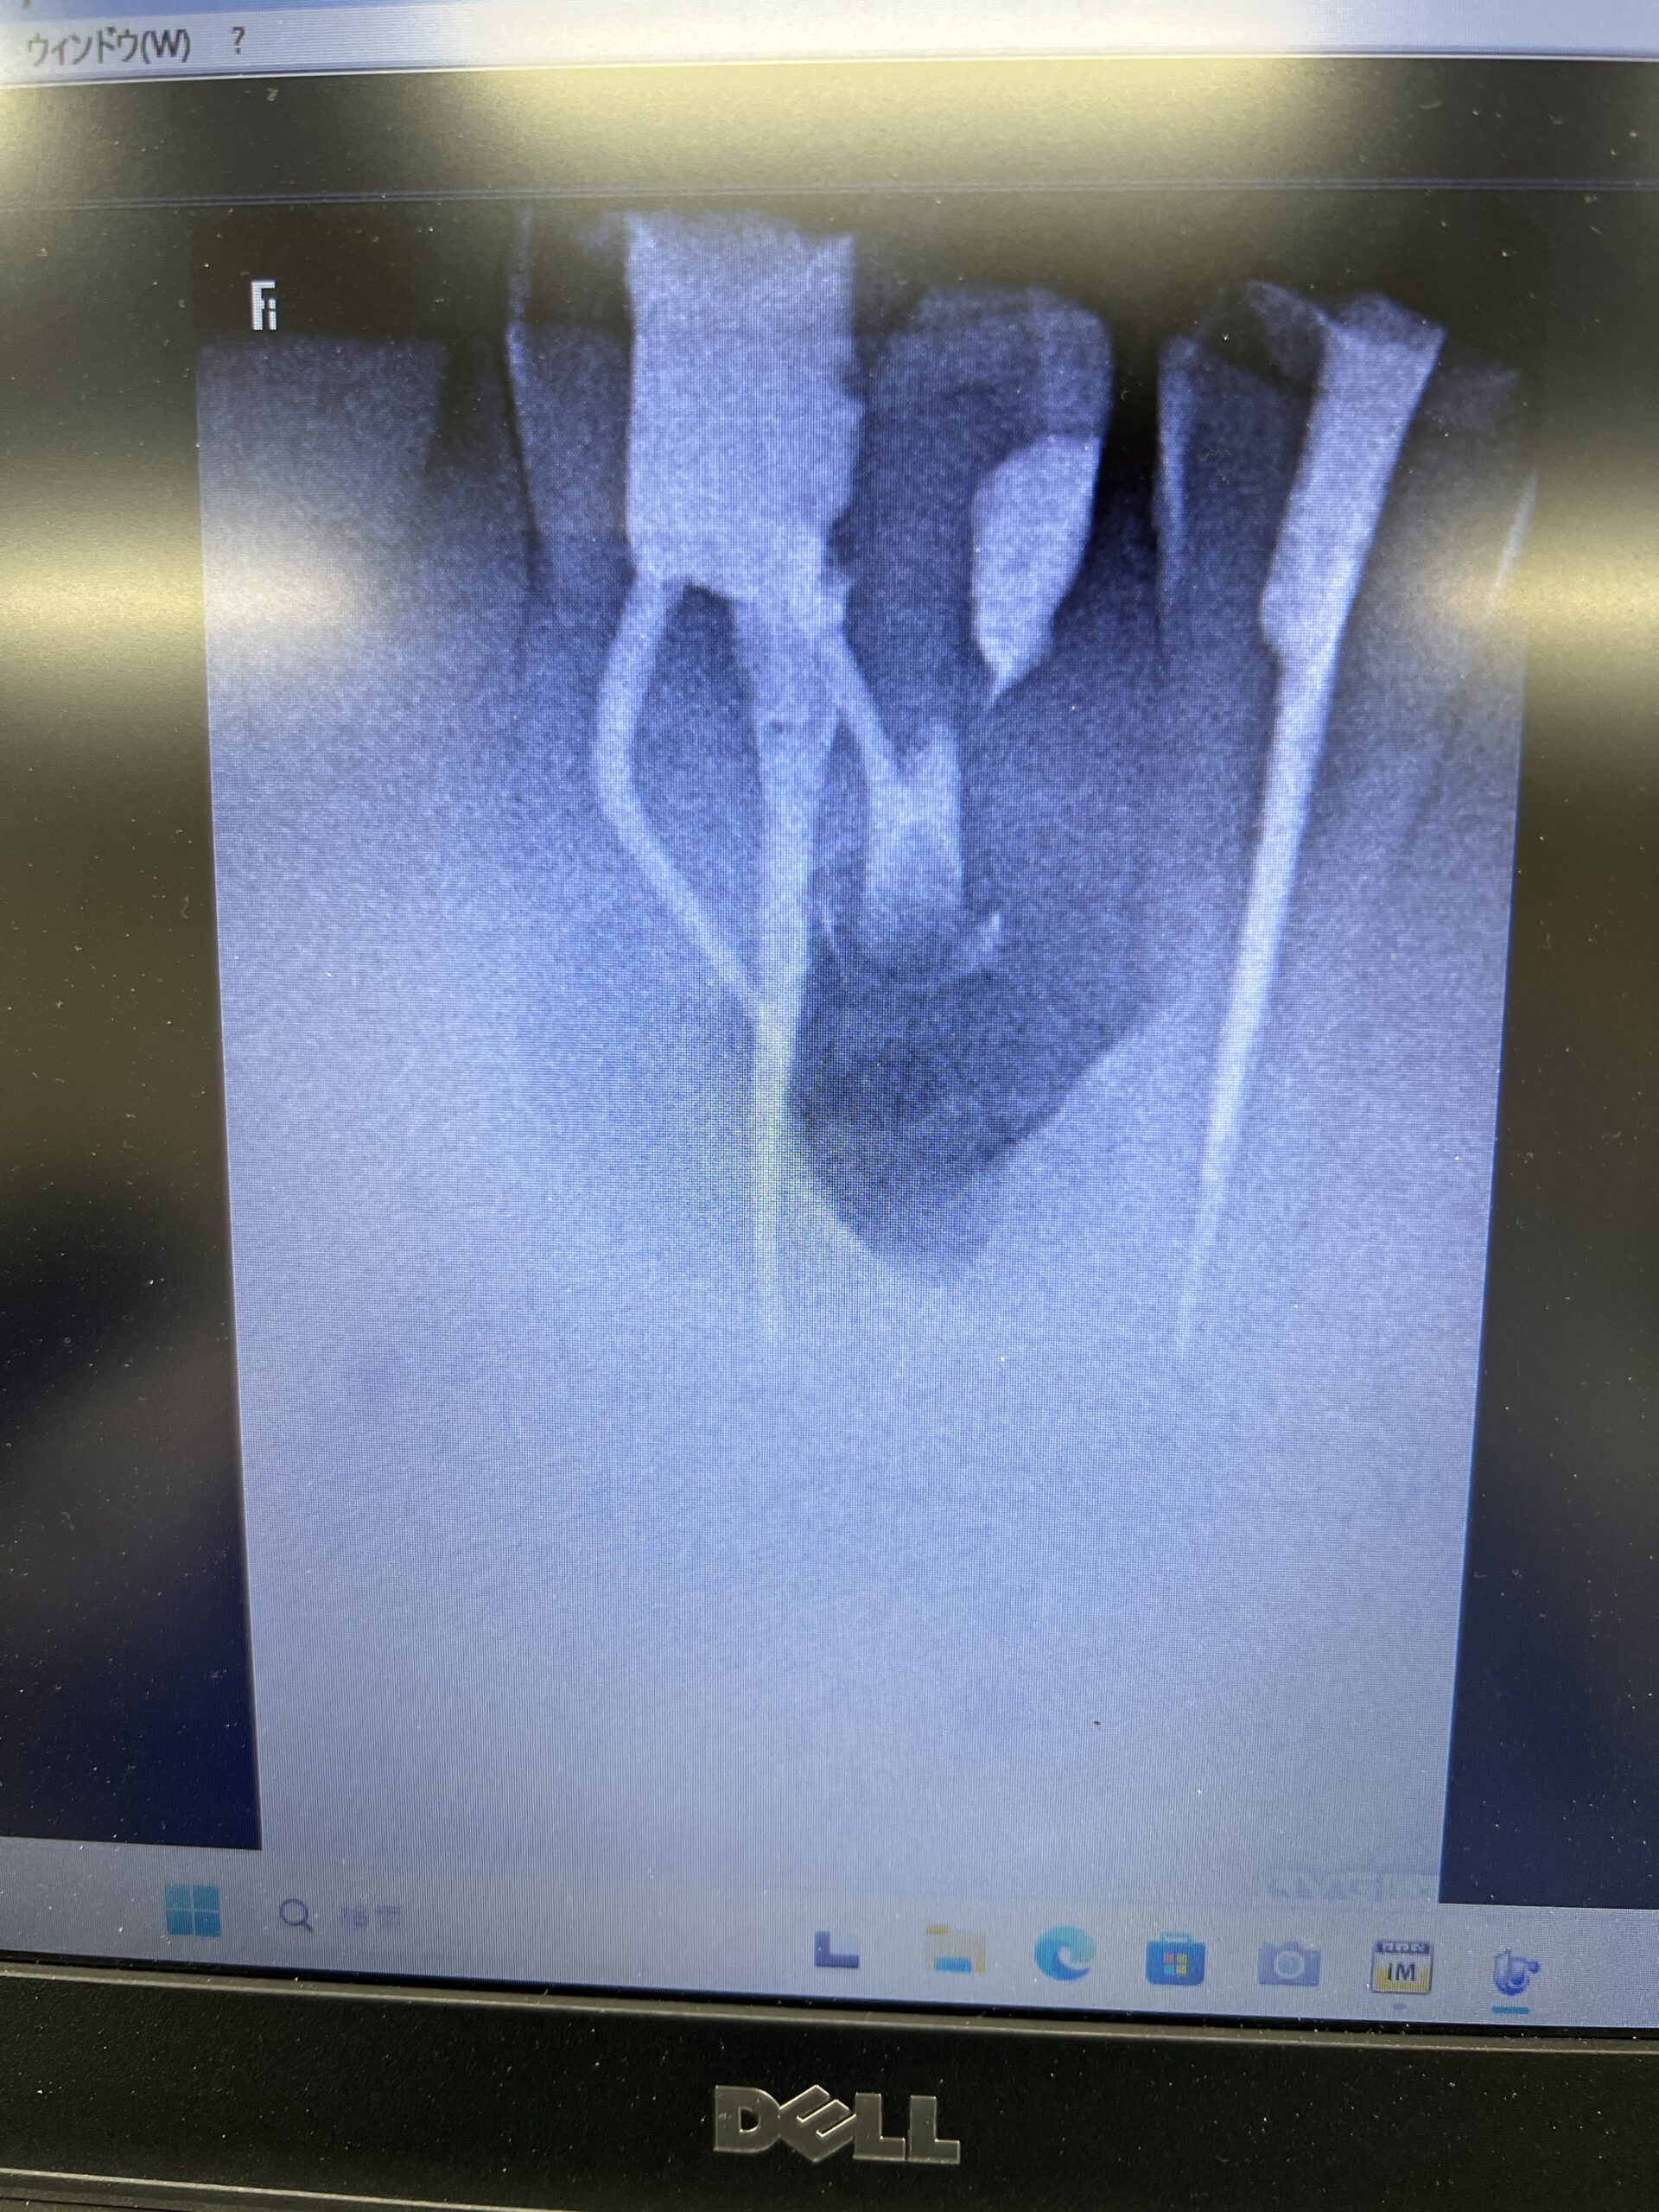

次の受講者は以下だ。

これでも治癒することはこのHPのBlogで示しているが、

他県(遠方)からの患者さん。。。前歯の歯茎が痛く、ここで治療すると1回で終了すると言われたので来た〜#7 Apicoectomyとその1yr recall

USCだとしょっぱいからやり直せと言われる案件だ。

この受講者は外科に関してはもう教えることはないだろう。